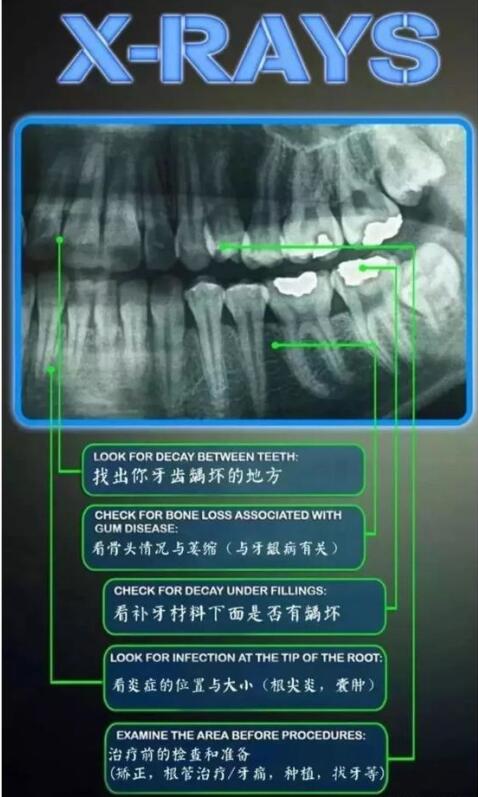

以上的办法可以减轻您的疼痛和减轻病症,建议您为了牙齿的健康,应该养成定期看牙医的习惯。提高牙齿的保健意识,牙齿的早期病变常没有明确的“警报”信号,但还是有一些提示的如进食冷热食物后胀痛不适、牙齿咀嚼无力、松动、牙龈出血牙齿间或酸软、食物嵌塞等,这些都可能是牙齿出现早期蛀牙、牙髓炎的表现。